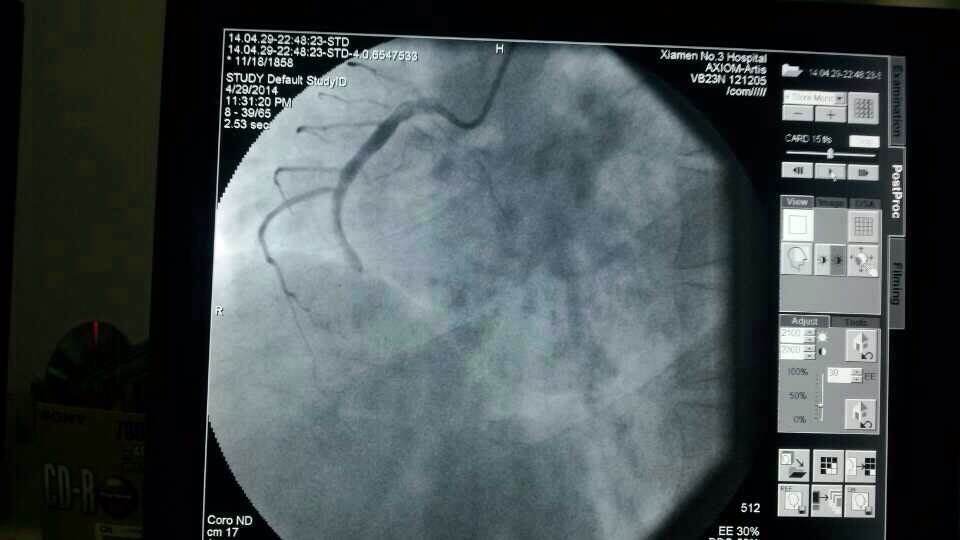

昨天仅一天的时间,厦门第三医院急诊接诊9名胸痛、心梗病人,其中一名河南来厦务工的男性患者,43岁,心脏大面积心梗;另一名翔安心梗患者送到三院时已经心衰终末期,但第三医院马上启动应急机制,心内科抢救技术团队第一时间到位,给予紧急打通血管,植入支架,才保住了两名患者的生命。